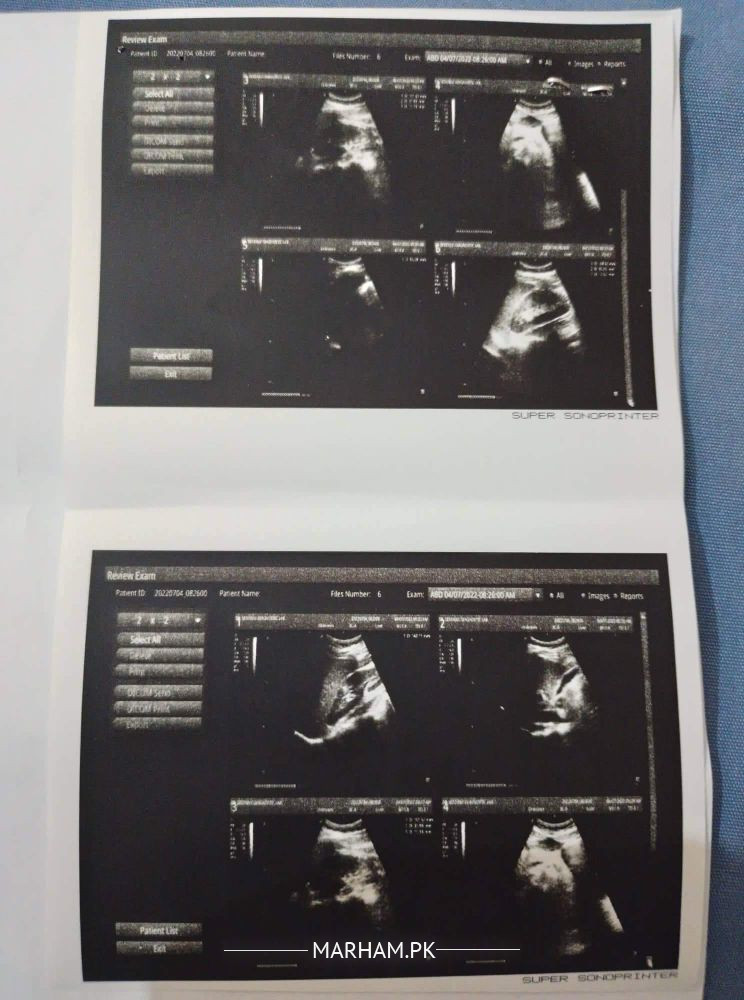

Mujjje right kidney ki side pe minor pain hota he or urine mujhe zada ata he or 1 time me full urine pass ni hota thori dair bad dobara mujhe urinate krne ki need parti he.. and ye reports hen kindly mujhe bata den is everything okay?

ultrasound is normal. only there is mild fullness in right kidney.. Your urine complete shows moderate bacteria in ur urine

and kindly also have ur CT KUB PLAIN done so that to look if there is any obstruction in urinary tract that is causing mild fullness (mild hydronephrosis) on right side